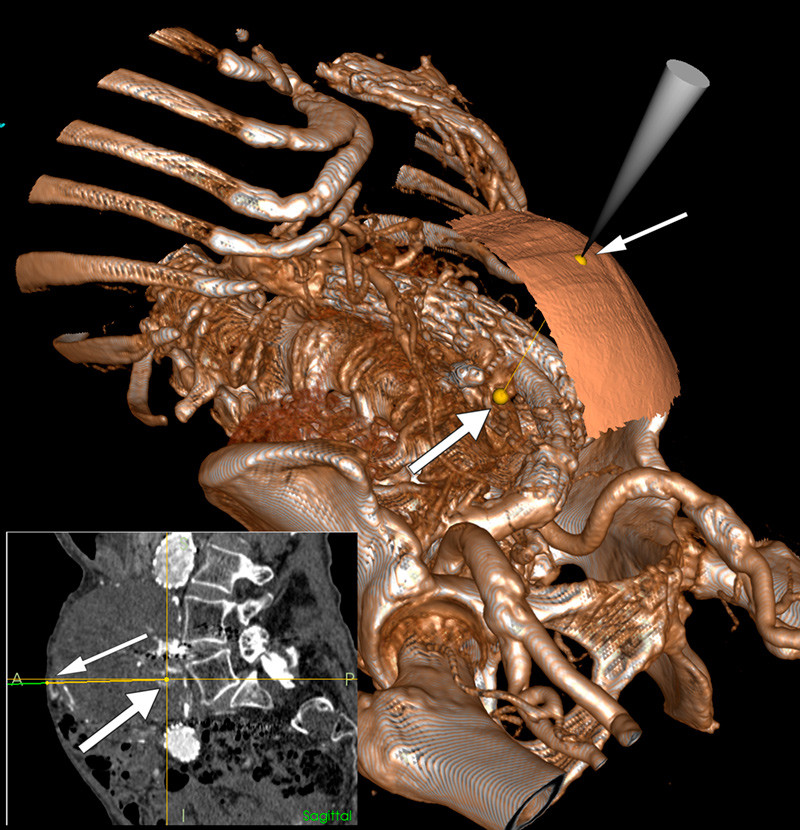

Nasjonalt kompetansesenter for ultralyd og bildeveiledet behandling har utviklet et navigasjonssystem (1) som kontinuerlig viser posisjonen til forskjellige instrumenter i et 3D-bilde. I en gjennomlysningsstue med integrert 3D-avbildningsutstyr kunne det ved hjelp av navigasjonssystemet utføres perkutan embolisering uten å måtte flytte pasienten. Stor figur viser et 3D-bilde av pasienten med nåletuppens plassering på hudoverflaten (tynn pil) og retning mot en av lumbalarteriene (tykk pil). Slik kan nålen plasseres optimalt og posisjonen kontrolleres underveis med mulighet for flere innstikk basert på samme bildeopptak. Liten figur viser samme oppsett i sagittalplanet. Mikrokateteret ble anlagt via nålen og lumbalarteriene embolisert med Onyx-injeksjoner. Kontroll halvannet år senere viste ingen lekkasje og uendret størrelse på aneurismet. Metoden er eksperimentell og del av et pågående forskningsprosjekt.